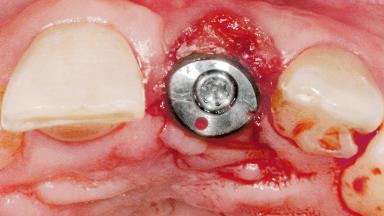

Late Flapless Placement of an Implant in a Maxillary Left Central Incisor Site

Type of Implants One-Piece

Abutment Type Standard

Prosthesis Type FDP